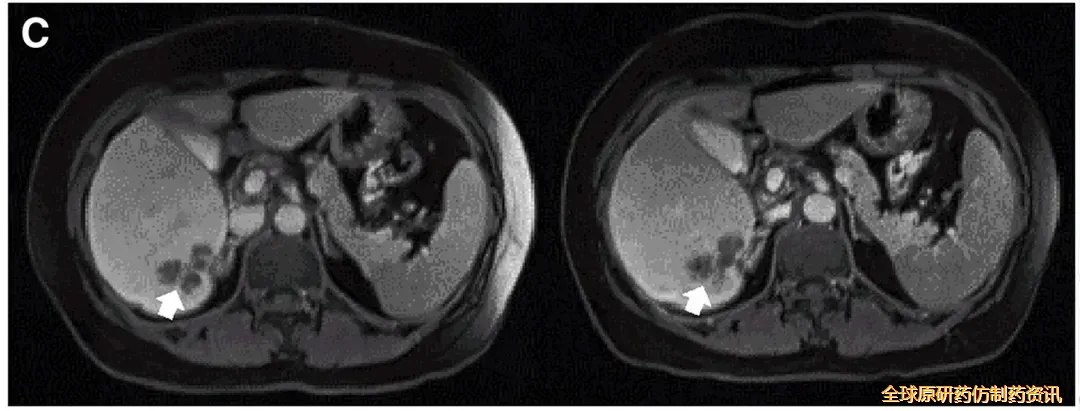

结果振奋人心:10例既往治疗进展(PD)的患者中,7例治疗后达到病情稳定(SD),肿瘤直径仅轻微变化,其中2例稳定状态持续超30周(7.5个月)。值得一提的是,其中一个典型病例(P10患者)在接受DL4剂量CEA CAR-T治疗后,MRI证实其肝内一处病灶明显缩小(详见下图)。

▼P10患者在CAR-T治疗前(左图)、治疗4周后(右图)的MRI对比

▲图源“Molecular Therapy”,版权归原作者所有,如无意中侵犯了知识产权,请联系我们删除